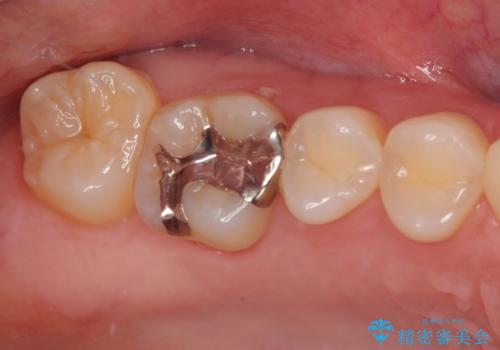

- 銀歯をやり替えたいとのことで来院された患者様です。金属の詰め物の大きさ、虫歯の範囲を考慮してセラミックの詰め物(セラミックインレー)で治療を行っていくことにしました。

拡大鏡視野下で、金属の詰め物(メタルインレー)、虫歯の除去を行い、セラミックインレーに適した形に整えました。